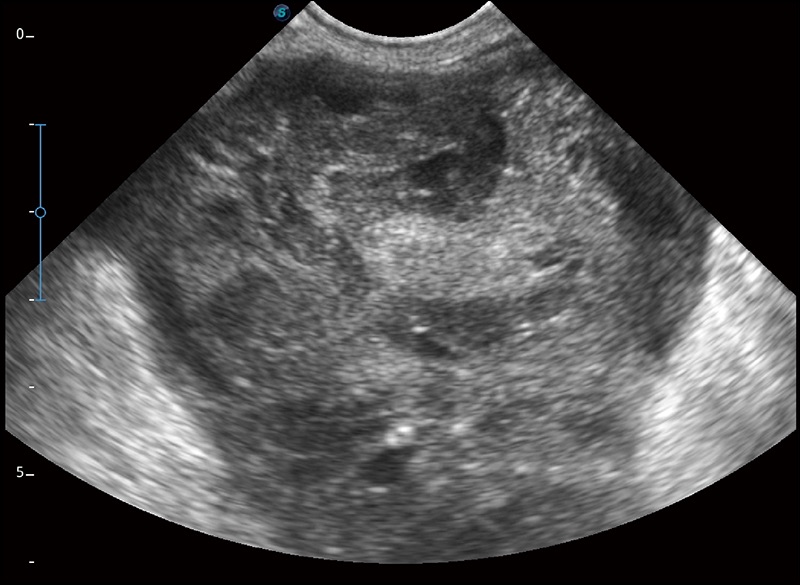

α1

精致轻巧 性能迅捷

α1卓越的图像质量和便捷的工作流程,使每位宠物医生都能轻松扫查。其全面的兽用应用功能和紧凑型的结构设计,可以满足动物检查的多种需要。专业的预设检查模式和多领域测量软件包有助于为不同类型的动物提供检查, 让宠物医生能够出色的完成工作。